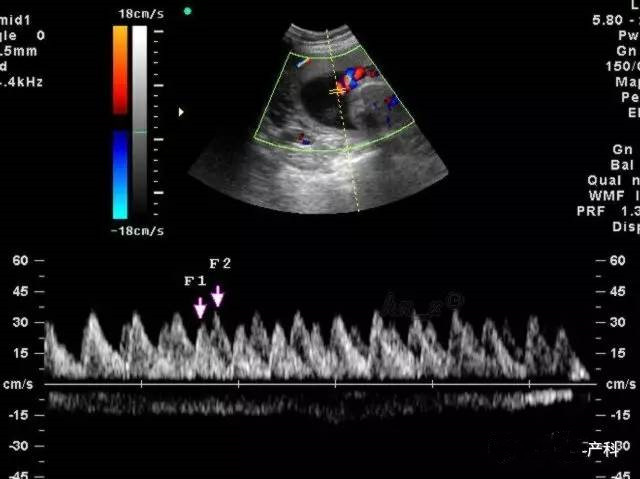

正常值跟怀孕的周数有关,主要有三项,以S/D值为主要指标,多以妊娠晚期S/D值小于或等于3.0作为正常值.脐血流和孕周时间有着密切的关系,一般随着孕周的增加,脐血流呈下降趋势,脐血流正常值在24周时其平均值为3.5,上限为4.25,超过此值为异常。可以使用脐动脉血流检测仪,在胎儿肢体侧探测脐动脉血流,内置软件根据所测S/D,PI、RI、FUR血流指标将自动测出血流阻抗分级。

RI:脐动脉血流阻力指数

S/D:脐动脉血流速度峰谷比

正常妊娠时胎儿的S/D、RI值随着妊娠时间推移呈降低趋势,尤其S/D值的变化是掌握胎儿发育是否正常的重要指标。